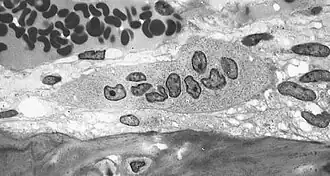

Osteoclasto (do grego para "osso" (Οστό) e "quebrado" (κλαστός)) é uma célula móvel, gigante e extensamente ramificada, com partes dilatadas, e é multinucleada. Os osteoclastos foram descobertos por Kolliker em 1873.[1]

Nas áreas de reabsorção de tecido ósseo encontra-se porções dilatadas dos osteoclastos, colocadas em depressões da matriz escavadas pela atividade dos osteoclastos e conhecidas como lacunas de Howship. Os osteoclastos tem citoplasma granuloso, algumas vezes com vacúolos, fracamente basófilo nos osteoclastos jovens e acidófilos nos maduros.

Estas células se originam de precursores mononucleados provenientes da medula óssea que, ao contato com o tecido ósseo, unem-se para formar os osteoclastos multinucleados. A superfície ativa dos osteoclastos, voltada para a matriz óssea, apresenta prolongamentos vilosos irregulares.

Os osteoclastos são células muito grandes, que tem cerca de 40 micrómetros de diâmetro. Possuem vários núcleos e são responsáveis pela destruição do osso. Quando a membrana celular dos osteoclastos entra em contato com a matriz óssea formam-se prejecções que constituem um bordo pelo qual entram íons hidrogênio para assim ser produzido um meio ácido que provocará a descalcificação da matriz óssea. Nos osteoclastos o retículo endoplasmático rugoso é escasso, e o complexo de Golgi é extenso.[2][3]